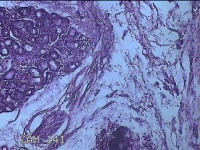

下唇包块

性别

女

年龄

38岁

临床诊断

唇粘液囊肿

一般病史

下唇包块1月。

标本名称

大体所见

灰白暗红色带皮肤样包块1.3x1x0.8cm一个,表面光滑,切开包块呈囊性,囊内充满大量粘液样物,囊壁厚0.1cm。

混合瘤